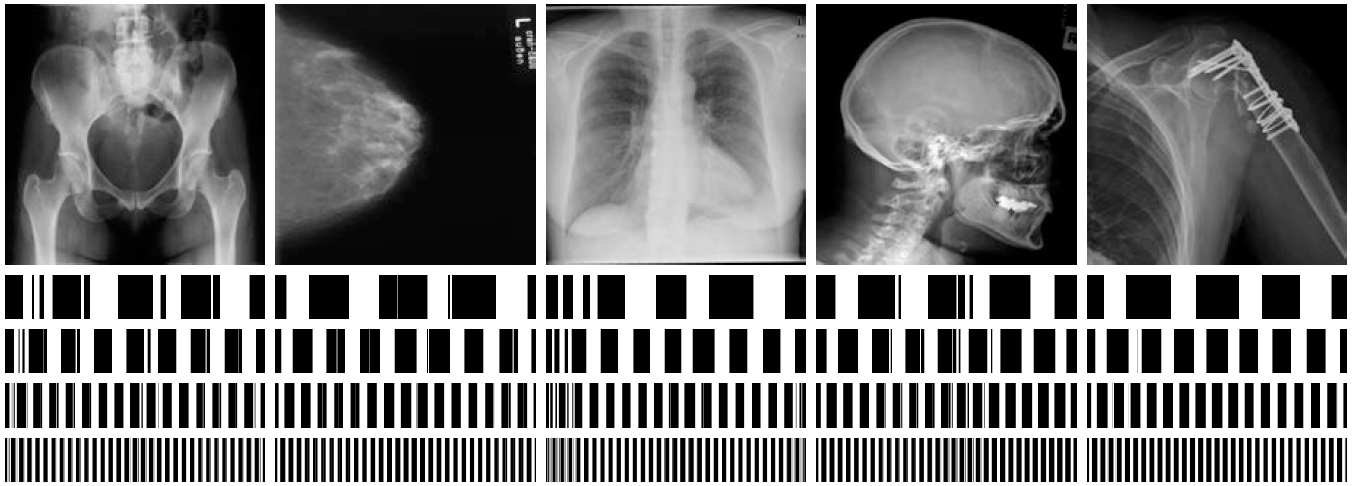

Refer to caption

Figure 1: Radon Barcode (RBC) [14] – Projections P1, P2, P3, and P4 are thresholded to generate code fragments C1, C2, C3 and C4. The concatenation of all code fragments delivers the barcode RBC.